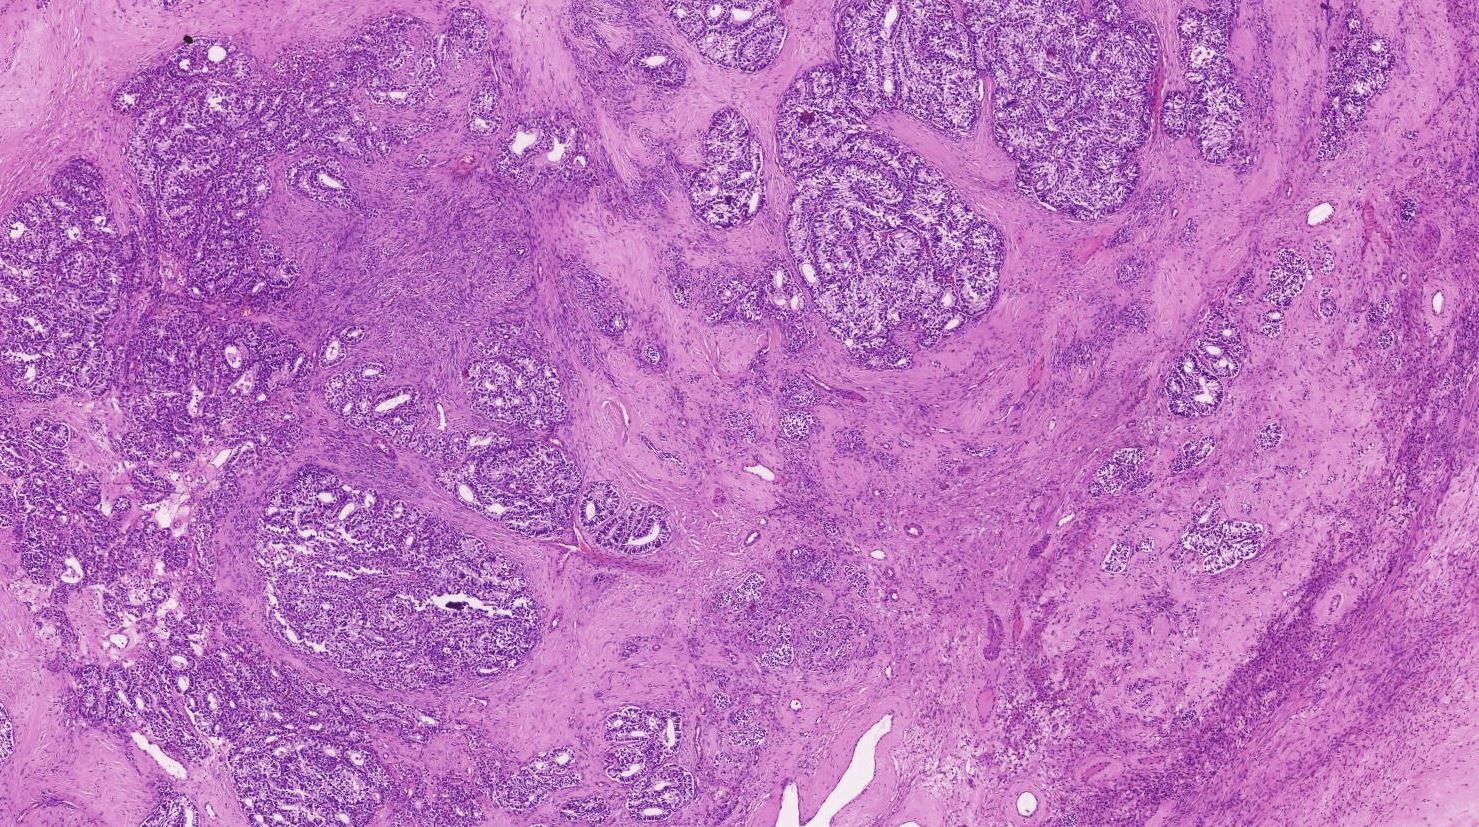

Presence of an ovarian tumour plus hormonal disturbances suggests a Sertoli–Leydig cell tumour. However, hormonal disturbance is present in only two-thirds of cases. A conclusive diagnosis is made via histology, as part of a pathology report made during or after surgery. See also sex cord–gonadal stromal tumour.

The tumour is subdivided into many different subtypes. The most typical is composed of tubules lined by Sertoli cells and interstitial clusters of Leydig cells.